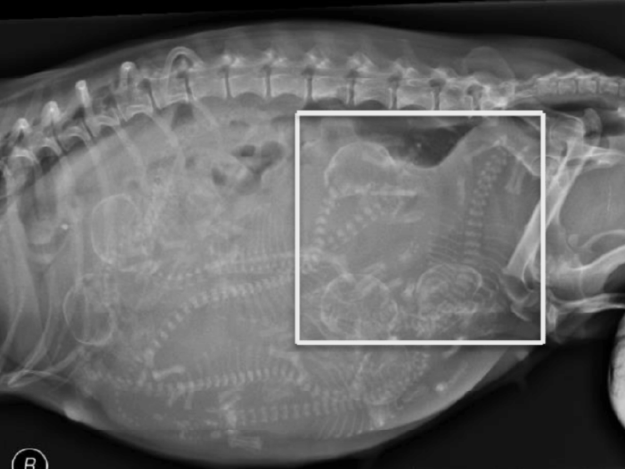

Cystotomy in Dogs and Cats